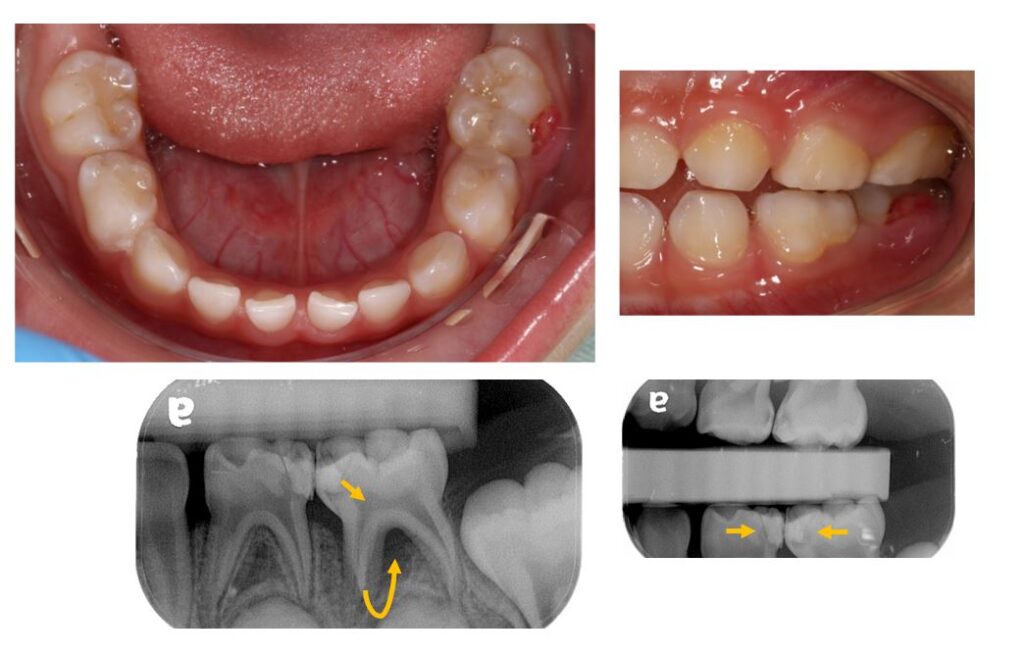

<figure class="wp-block-image size-large"><img loading="lazy" decoding="async" width="1024" height="740" src="https://wellnews.media/wp-content/uploads/2023/03/gout-2-1024x740.jpg" alt="" class="wp-image-6760" srcset="https://wellnews.media/wp-content/uploads/2023/03/gout-2-1024x740.jpg 1024w, https://wellnews.media/wp-content/uploads/2023/03/gout-2-300x217.jpg 300w, https://wellnews.media/wp-content/uploads/2023/03/gout-2-768x555.jpg 768w, https://wellnews.media/wp-content/uploads/2023/03/gout-2-1536x1110.jpg 1536w, https://wellnews.media/wp-content/uploads/2023/03/gout-2-2048x1480.jpg 2048w, https://wellnews.media/wp-content/uploads/2023/03/gout-2-324x235.jpg 324w, https://wellnews.media/wp-content/uploads/2023/03/gout-2-696x503.jpg 696w, https://wellnews.media/wp-content/uploads/2023/03/gout-2-1068x772.jpg 1068w, https://wellnews.media/wp-content/uploads/2023/03/gout-2-581x420.jpg 581w, https://wellnews.media/wp-content/uploads/2023/03/gout-2-1920x1387.jpg 1920w" sizes="(max-width: 1024px) 100vw, 1024px" /><figcaption class="wp-element-caption"><strong>痛風患者手部X光片，紅圈為痛風石，黃色箭頭為遭破壞骨頭。(圖/花蓮慈濟醫院堤供)</strong></figcaption></figure>